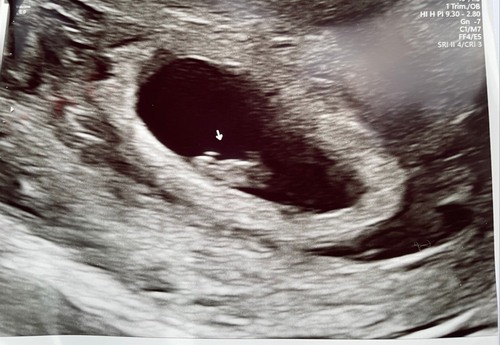

Ramzi is (weliswaar niet betrouwbaar maar wel leuk) een theorie die TOT 8 weken gebruikt kan worden door te kijken waar de placenta ontwikkeld.

Deze foto's geven alleen niet voldoende beeld van de baarmoeder om het te kunnen zien naar mijn mening. Heeeeeeeel misschien iets eerdee rechts en dan zou het met inwendige echo een jongetje zijn volgens de theorie.

Als je Ramzi moet geloven ontwikkeld de placenta vaak rond de vrucht dus dat zou bij jou links zijn. Je hebt een uitwendige echo gehad dus de ramzi zou dan voor nu zeggen een jongen, geloof ik. 😅

Jaa dat maakt het aan jou echo lastig. Ook dat je niet een totaal plaatje hebt van je hele baarmoeder. 😅 aangezien je een inwendige echo hebt gehad moet je de theorie omdraaien. In jou geval is rechts een jongen en links een meisje, maar jou vruchtje twijfelt nog 😂